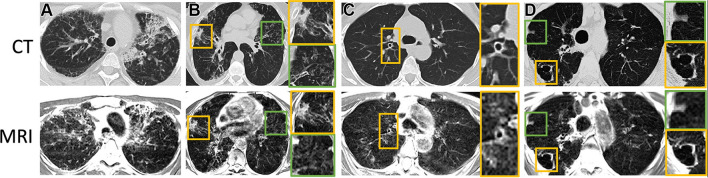

At low field, lung parenchyma T2/T2* values are greatly prolonged, providing high SNR efficiency. Li et al. [55] jointly measured the lung parenchyma T2/T2* with an echo-shifted multi-echo spin echo pulse sequence, determining the normative values of lung parenchyma are T2 = 68.6 ms and T2* = 8.2 ms. Notably, the T2* is 5–10 times larger than at 1.5 T (2.11 ms) or 3 T (0.74 ms) [56]. This greatly improves the capability of performing lung imaging at low field strengths, and many opportunities are emerging. Campbell-Washburn et al. [57] demonstrated diagnostic image quality with a T2-weighted spin echo sequence in a small cohort of patients (N = 24) with various lung conditions, with representative examples shown in Fig. 3. T2-weighted sequences at 0.55 T provide important structural assessments of many lung conditions. Combined with a diffusion weighted imaging, differentiation of benign and malignant lung nodules was also possible [58]. T2-weighted structural images were also used to assess pulmonary ground glass and fibrosis-like opacities associated with COVID-19 [59–61]. Hinsen et al. [62] compared lung nodule detection between 0.55 T MRI and CT. In 964 total nodules of 46 patients, MRI had 100% accuracy in detecting nodules of size ≥ 6 mm, 80% (159/200) for those ≥ 4 and < 6 mm, and 23% (147/638) for those < 4 mm.

Fig. 3.

Axial CT (reformatted to 0.8 × 0.8 × 6 mm) and T2-weighted MR (reformatted to 1.1 × 1.1 × 6 mm) images show A honeycombing, interstitial thickening, and fibrotic changes in a 35-year-old woman; B consolidative opacities in a 70-year-old woman; C bronchial wall thickening with bronchiectasis in a 58-year-old woman; and D a cavitary lesion in a 70-year-old woman. B–D Green and yellow boxes on CT and MR images denote the area of interest around the particular finding described, with the corresponding box bordered in that color to the right of the respective image showing an enlarged view of the area. Image is reproduced from Campbell-Washburn et al. [57]